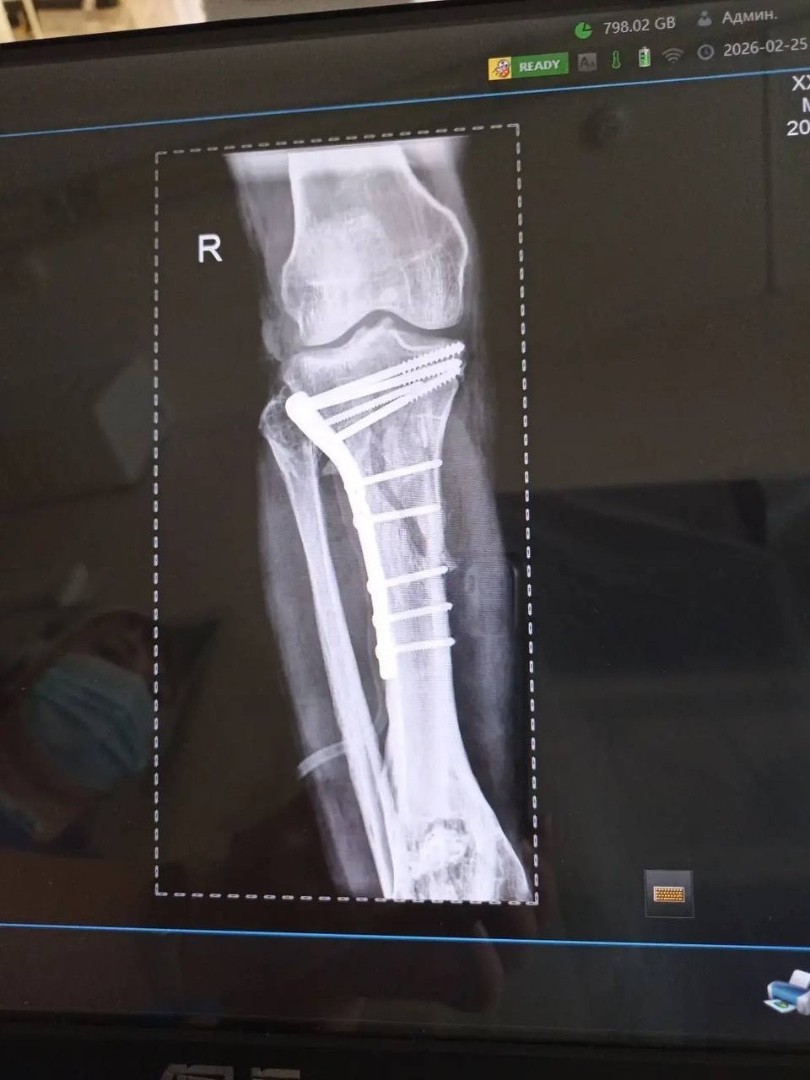

Травматологи горбольницы «Липецк - Мед» почти три часа буквально по кусочкам собирали голени пациента после аварии!

Пациент поступил после тяжелого ДТП 25 февраля с внутрисуставными переломами верхних зон обеих голеней.

Ситуация осложнялась хронической анемией на фоне кровопотери, что требовало особого подхода и скорости.

Заведующий отделением травматологии Дмитрий Соколов с ассистентом, врачом - травматологом Евгением Крюченковым провели одномоментное оперативное  вмешательство на двух конечностях с интраоперационной гемотрансфузией. То есть, оперировали одновременно обе ноги с минимальной кровопотерей.